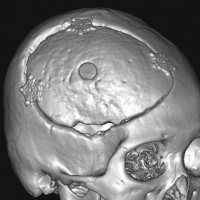

骨内髄膜腫 osseous meningioma

骨内増殖をする髄膜腫です。頭蓋骨腫瘍と間違えるようなものです。触った感じは骨腫ですが,CTでは,表面が毛羽立っていて,頭蓋冠に浸潤していることが特徴です。浅側頭動脈からの豊富な血流があります。

わずかですが頭蓋内にも腫瘍があり,硬膜が肥厚してガドリニウム増強されます。

頭蓋骨をかなり広範におかすので骨は捨てません。開頭して取り外した骨の厚くなっている部分と髄膜腫で軟らかくなっている部分を削除して,それから骨片をオートクレーブで短時間熱処理して,元あった所にもどします。下の画像は手術後1年半が経過したものですが,髄膜腫の再発はなく,熱処理骨弁は吸収されないで生着しています。